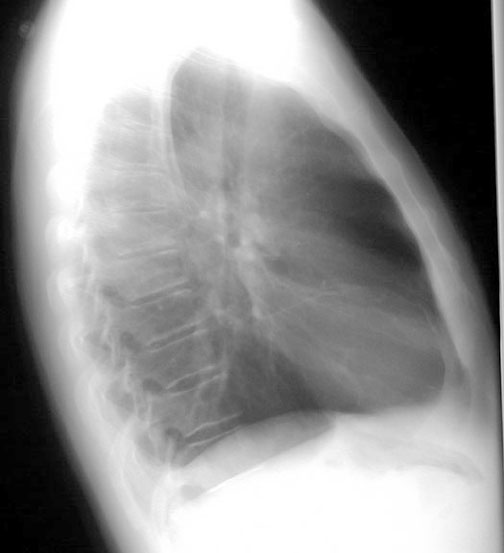

Lateral